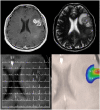

Advances in metabolic imaging techniques have allowed for more precise characterization of gliomas, particularly as it relates to tumor recurrence or pseudoprogression. Furthermore, the emerging field of radiogenomics where radiographic features are systemically correlated with molecular markers has the potential to achieve the holy grail of neuro-oncologic neuro-radiology, namely molecular diagnosis without requiring tissue specimens. In this section, we will review the utility of metabolic imaging and discuss the current state of the art related to the radiogenomics of glioblastoma.